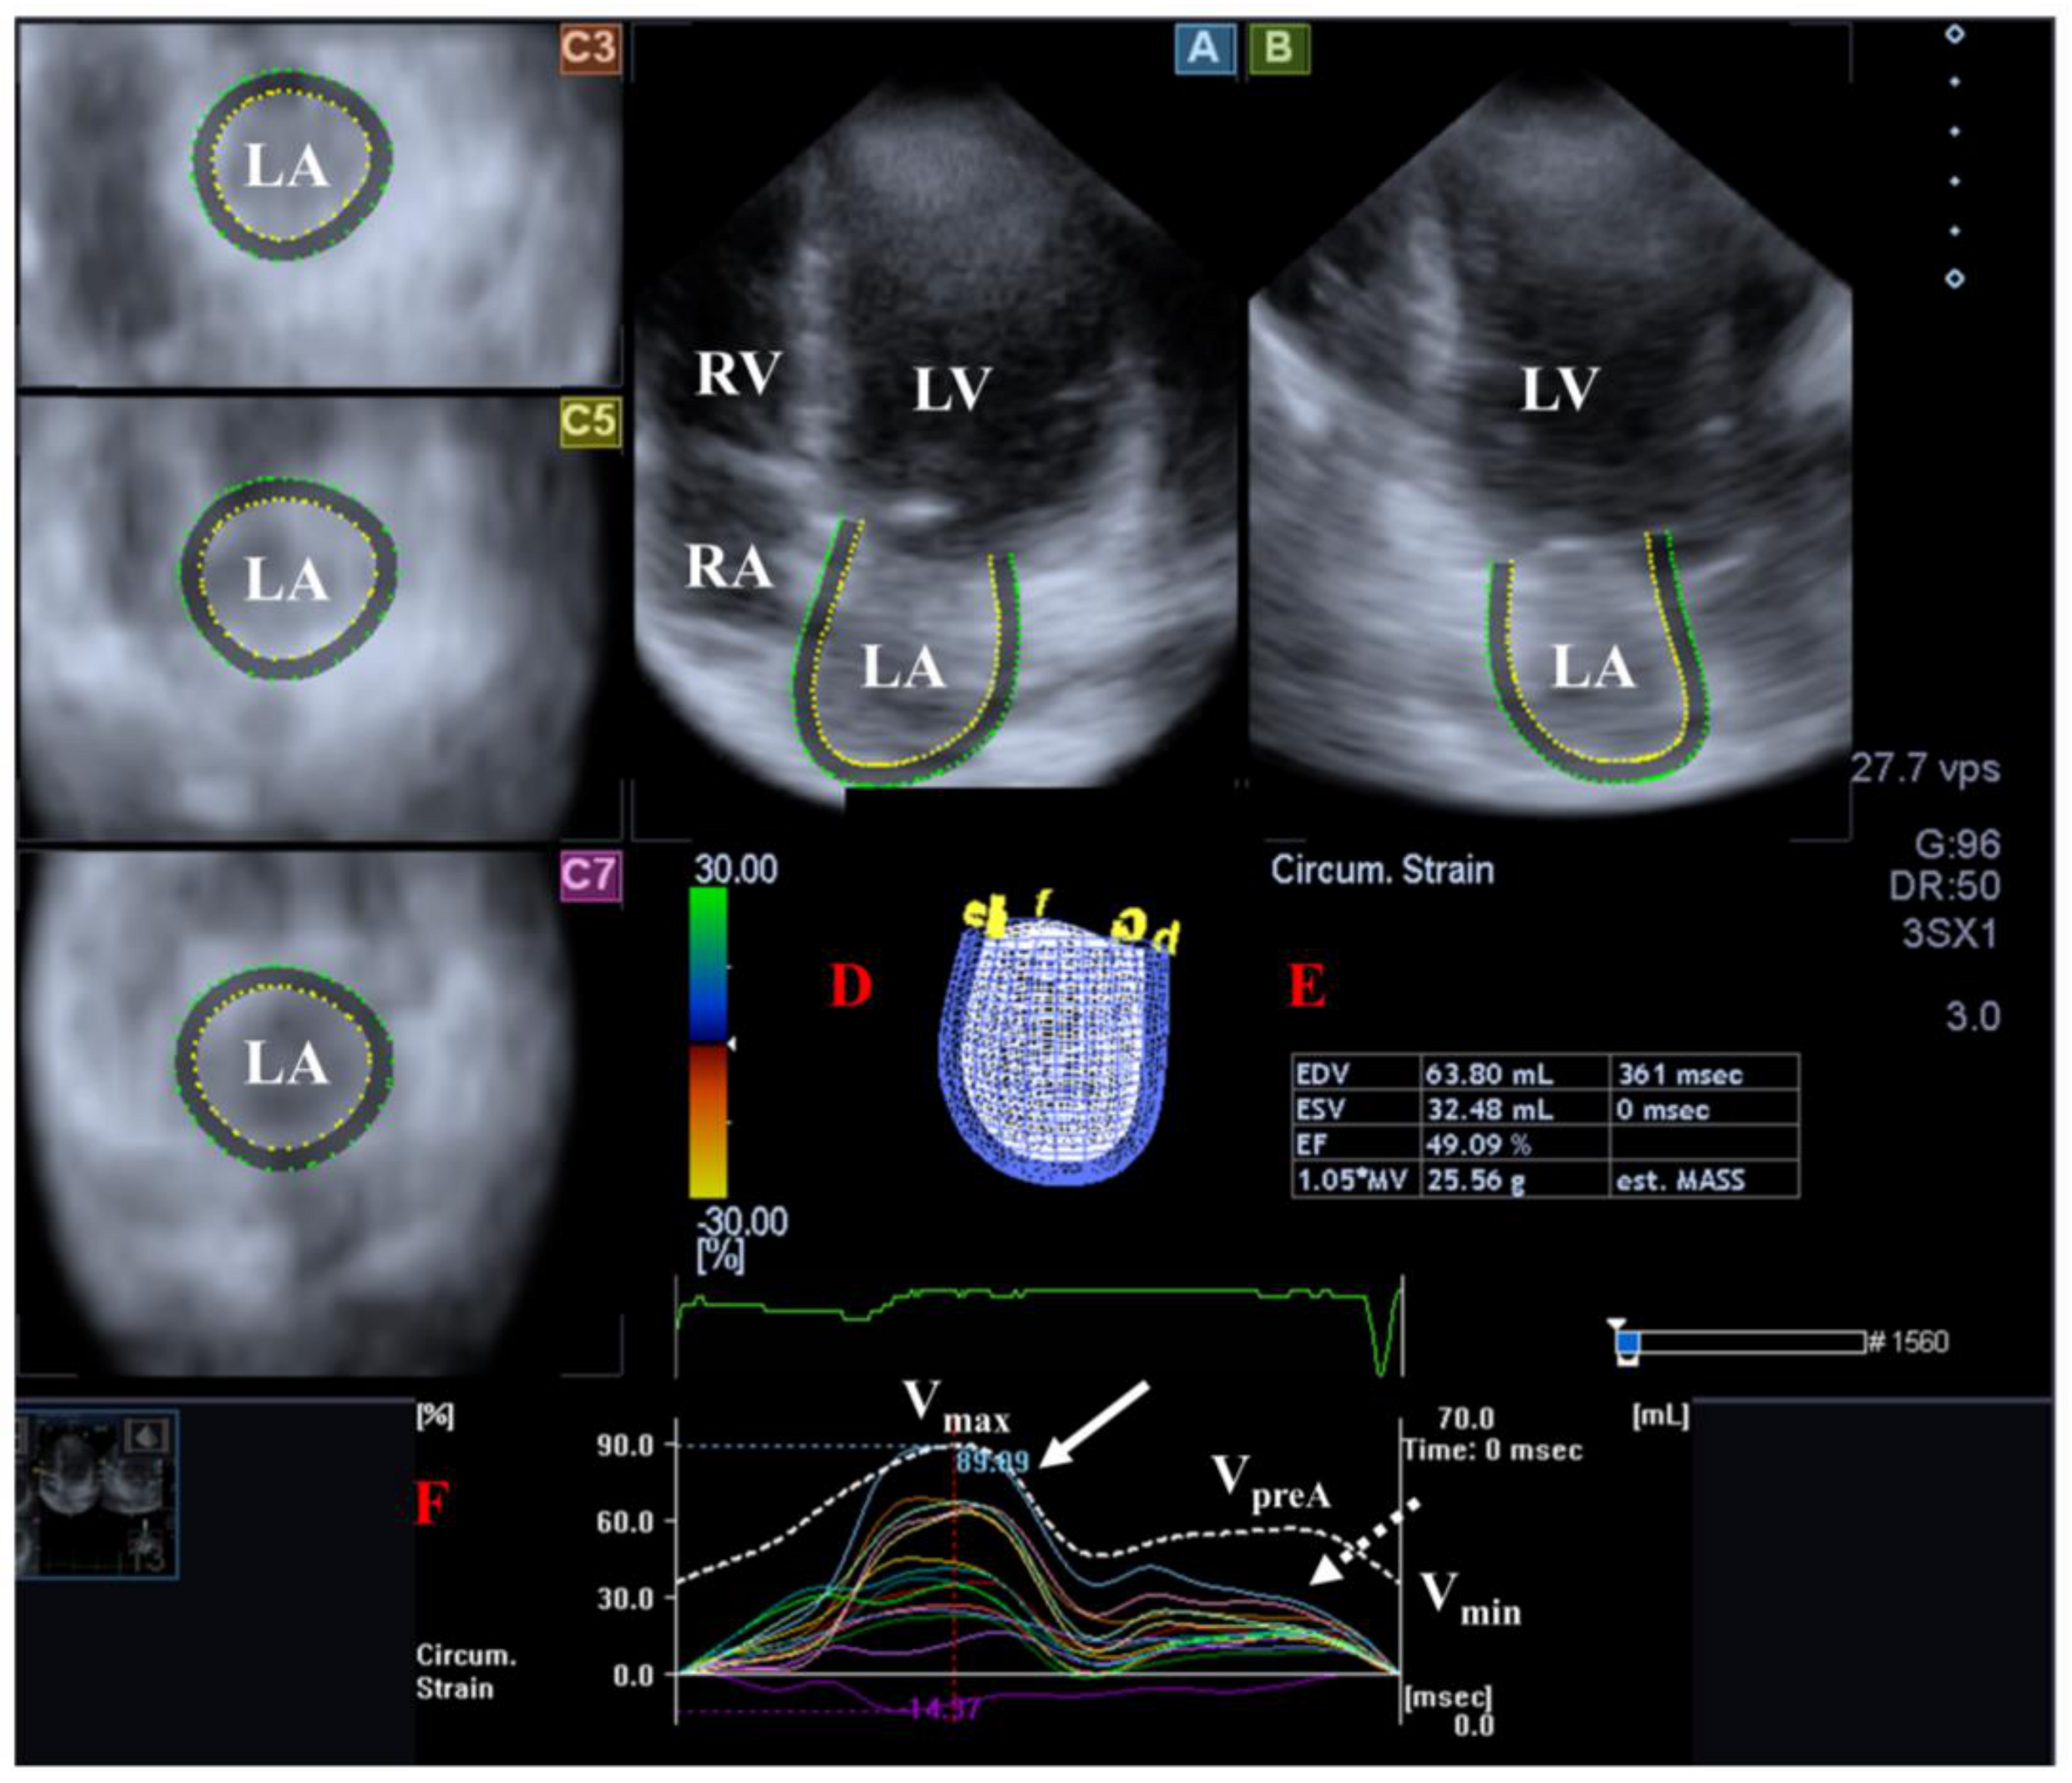

The muscle fibers of the LA run in circumferential and longitudinal directions. There are several phases of LA function including reservoir (in systole, its volume is highest), conduit (in early diastole) and booster pump (in late diastole, its volume is lowest). The Frank–Starling mechanism has significance in shaping the function of LA [53,54,55] (Figure 2).

Figure 2.

Examination of the left atrium [LA] by three-dimensional [3D] speckle-tracking echocardiography. Following echocardiographic data acquisitions, the following typical views are created: (A) Apical 4-chamber and (B) two-chamber longitudinal views and (C3,C5,C7) cross-sectional views at basal, midatrial and superior levels, respectively. LA can be easily detected alongside other heart cavities including the left ventricle [LV] and the right atrium [RA] and ventricle [RV]. A number of other details were also presented including (D) 3D cast, (E,F) maximum [Vmax], preatrial contraction [VpreA] and minimum [Vmin] volumes of the LA and curves representing changes in volumes and strains of LA over time. Reservoir [peak] and active contraction LA strains are represented by white and dashed white arrows, respectively.